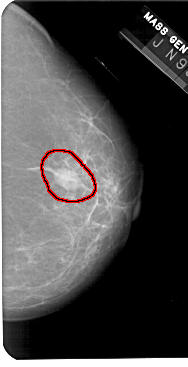

A_1436_1.LEFT_CC

FILE: A_1436_1.LEFT_CC.OVERLAY

TOTAL_ABNORMALITIES 1

ABNORMALITY 1

LESION_TYPE MASS SHAPE ARCHITECTURAL_DISTORTION MARGINS ILL_DEFINED

ASSESSMENT 4

SUBTLETY 3

PATHOLOGY BENIGN

TOTAL_OUTLINES 1

BOUNDARY